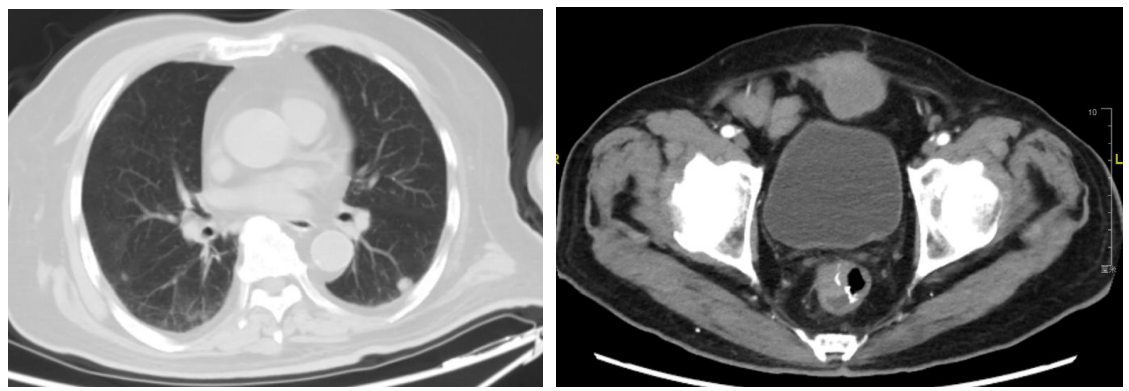

CT示直肠壁增厚,下腹壁肿块及左肺下叶结节(图2)。2023年3月3日肠镜提示直肠癌术后复发,病理示中分化腺癌。

直肠腺癌;腹壁继发恶性肿瘤;肺继发恶性肿瘤;高血压;2型糖尿病。

治疗3周期后复查,肿瘤标志物显著下降并维持低水平。CT提示腹壁包块缩小,疗效评估为部分缓解(PR)。

截至2025年10月,患者一线治疗PFS已达31个月,生活质量良好。

病例小结

该患者为81岁高龄男性,直肠癌术后复发伴多发转移,合并多种基础疾病。一线治疗采用TAS-102联合贝伐珠单抗方案,获得了超过31个月的PFS,远超传统一线治疗预期。治疗期间患者耐受性极佳,未出现严重不良反应(图3)。